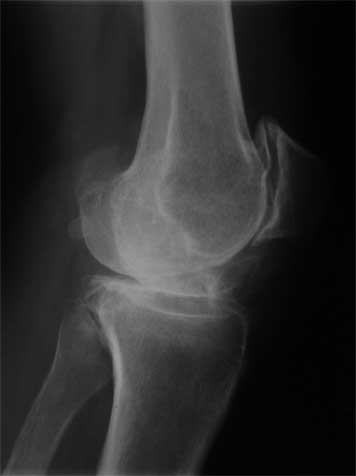

Вложение не в текстовом формате было извлечено…

Имя     : 3..jpg

Тип     : image/jpeg

Размер  : 14532 байтов

Описание: отсутствует

Url     : http://weborto.net:8080/pipermail/ortho/attachments/20090513/64886c60/attachment-0005.jpg